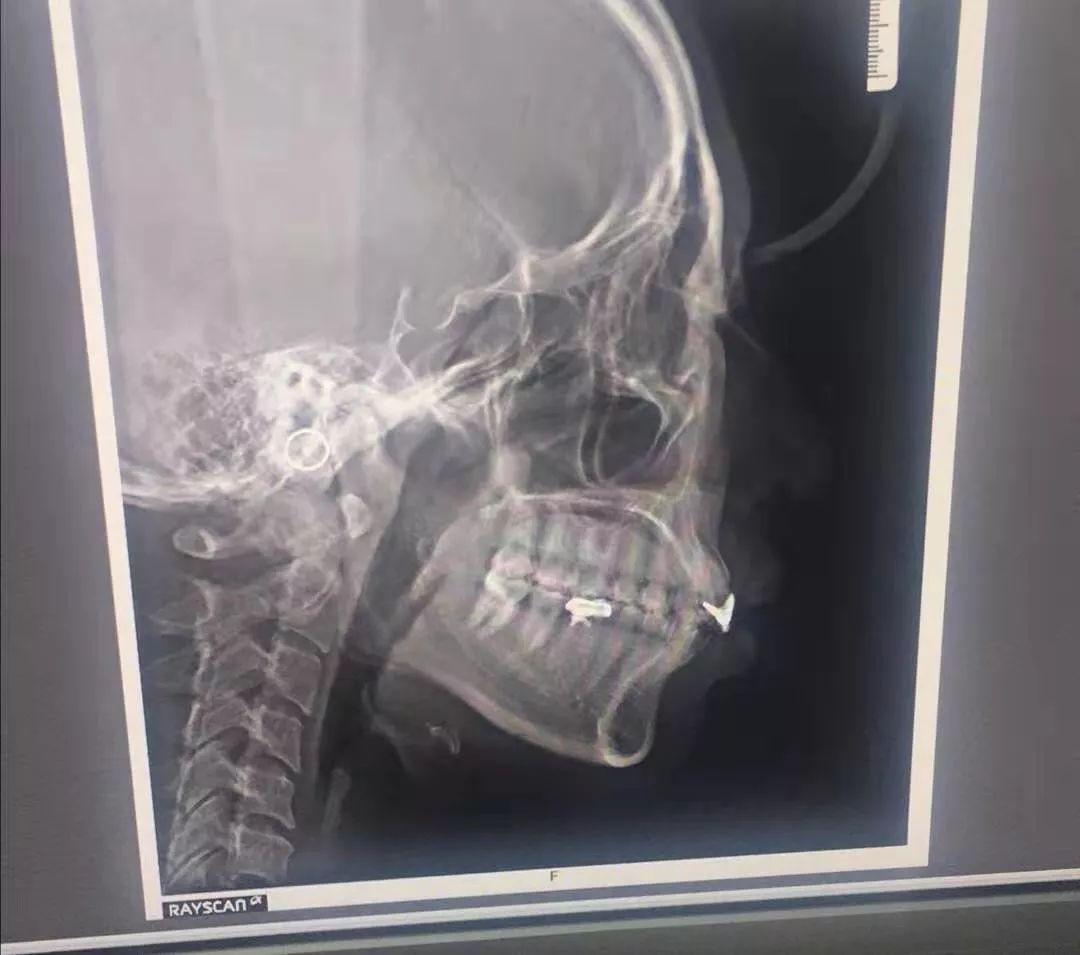

牙齿 X 光片

医生说我原本补过牙,不适合传统牙齿矫正,而且隐形矫正还能帮我矫正牙龈突出的问题。这简直是天大的好消息!